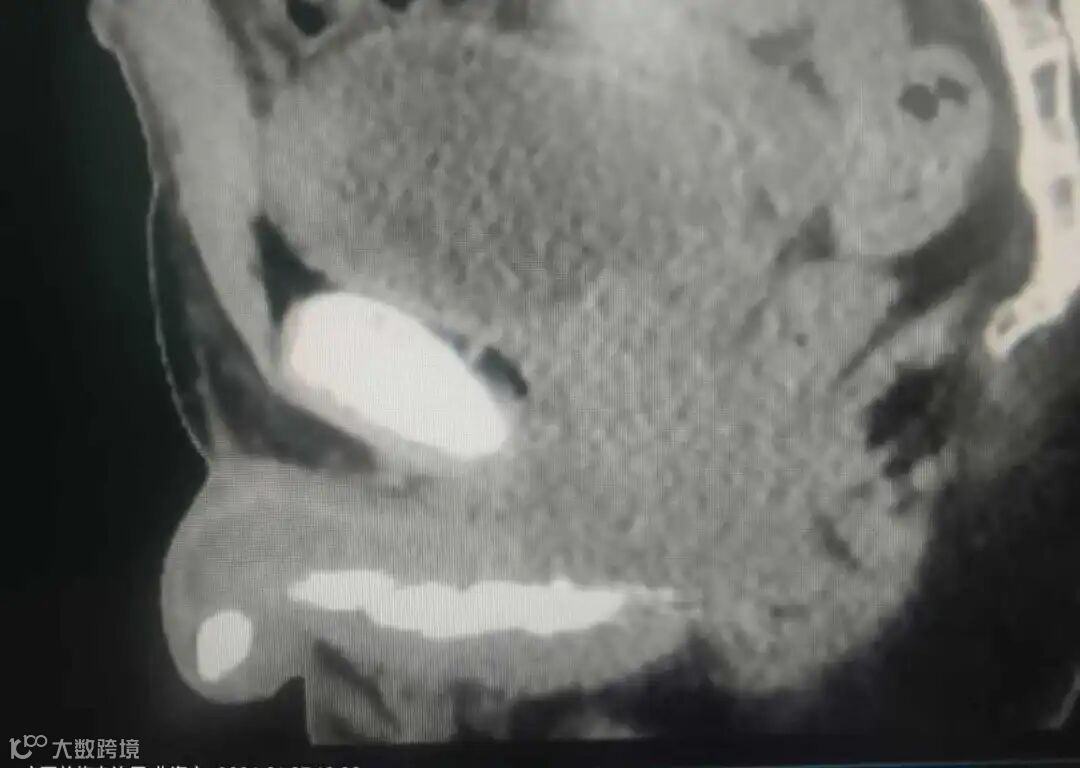

据了解,该患者在常规处理肾脏问题期间,医生通过影像检查发现其盆腔存在脓肿,同时尿道区域有异常高密度影。“最初从CT上看,尿道里有一串串的东西,形状不规则,我们以为是罕见的尿道多发结石。”泌尿外科主任陆顶进回忆。

随着进一步探查,真相逐渐浮出水面。内镜首先发现了两个状如笔帽头的圆筒状异物,其后方还有大量疑似结石的堆积物。由于患者当时肾脏感染严重,医疗团队决定先行处理肾脏问题,并将尿道内存在严重异物的情况告知患者,待其情况稳定后再行处理。

待患者肾脏情况稳定后,第二次手术专为清除尿道异物而开展。手术开始时,医生本以为只需取出前端的两个“圆头”异物并击碎后方结石,但操作起来才发现情况异常复杂。